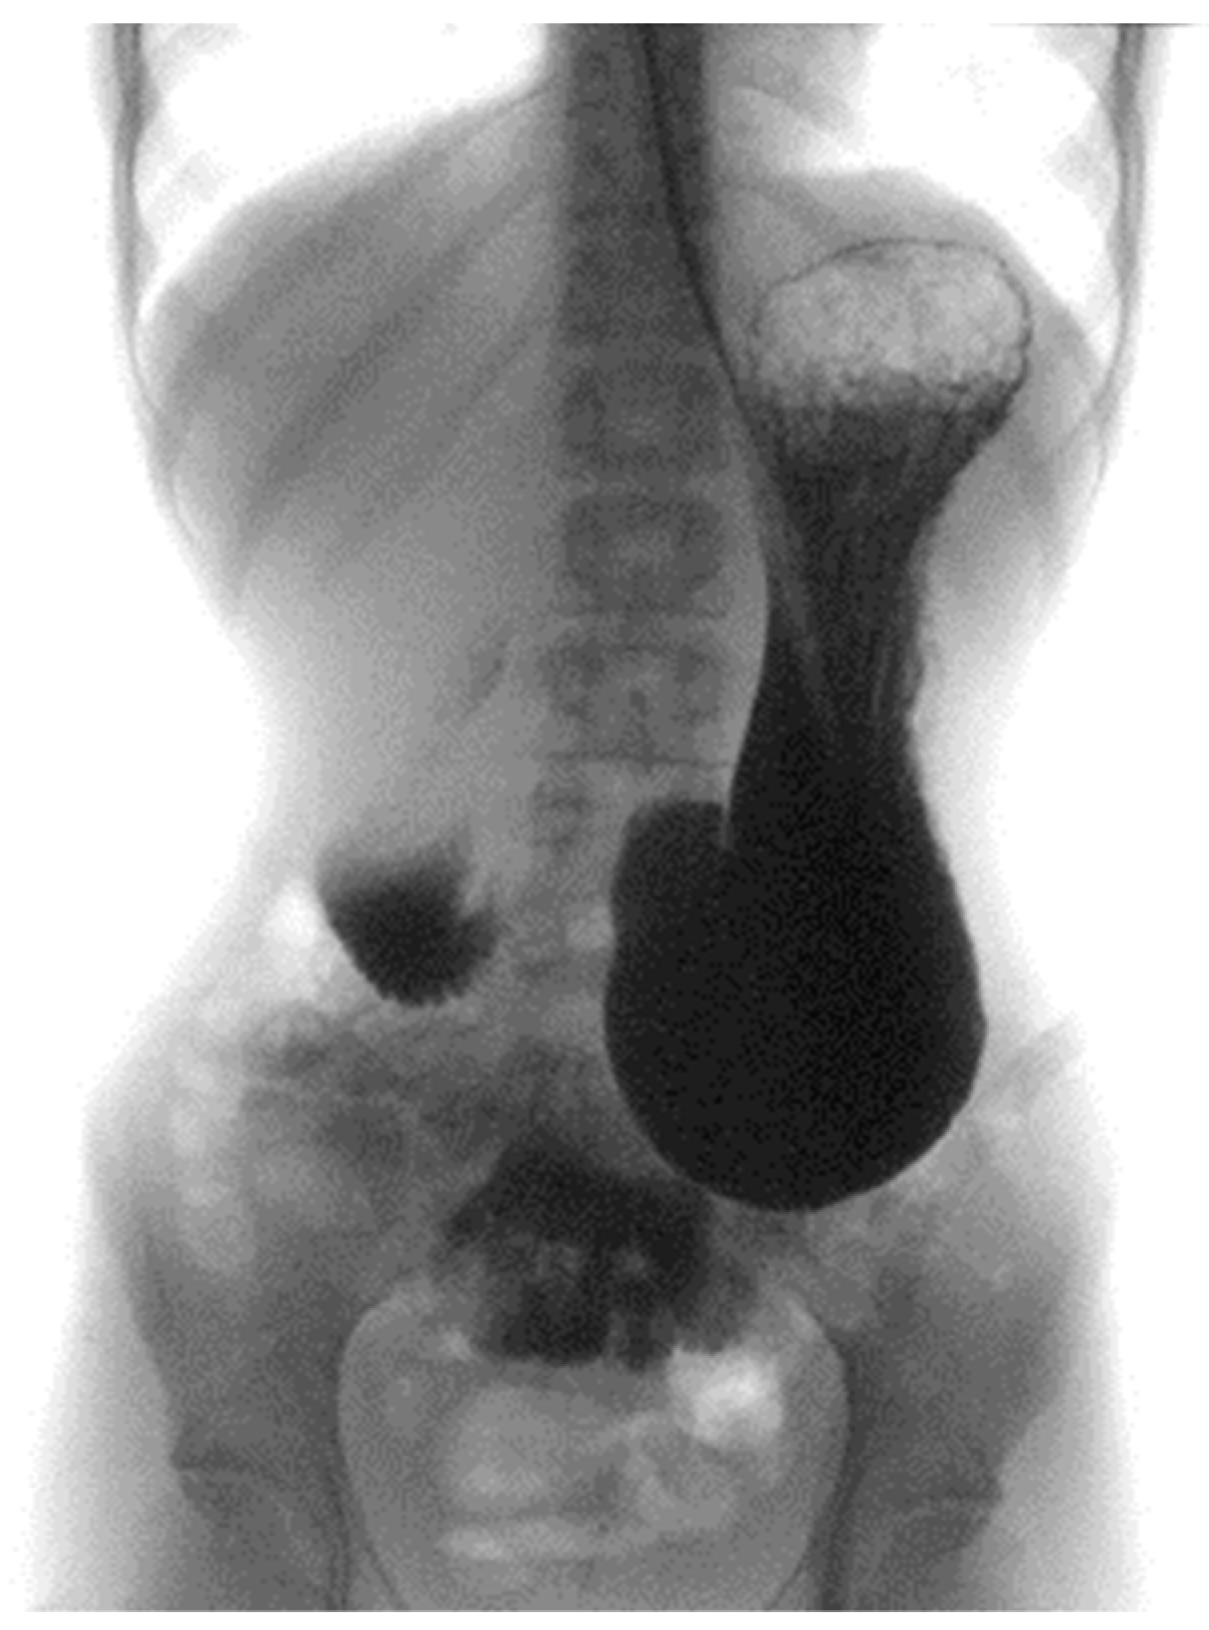

| Case index | Acute | Weight loss, Vomiting | 5 months | Upper gastrointestinal endoscopy | ||||

| 4 (Elbadaway MH et al.) [8] | Chronic | Weight loss, Heartburn, Abdominal pain, Post-prandial vomiting | 4 years | X-ray fluoroscopy | ||||

| 5 (Sours JA et al.) [9] | Chronic | Weight loss, Nausea, Post-prandial vomiting, Abdominal distension | 6 months | X-ray | ||||

| 7 (Froese AP et al.) [11] | Acute | Weight loss, Nausea, Vomiting | 13 months | X-ray | ||||

| 8 (Stheneur C et al.) [12] | Chronic | Weight loss, Nausea, Post-prandial vomiting, Abdominal pain, Abdominal distension | 6 months | X-ray | ||||